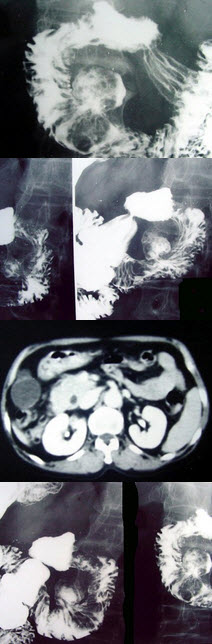

C.皮肤骨膜肥厚症

D.马方(Marfan)综合征

E.重型石骨症

44、多项选择题 胰头癌低张十二指肠造影的X线征象为()

A.十二指肠曲扩大

B.十二指肠曲缩小

C.十二指肠内缘呈反“3”字征

D.十二指肠内缘双边征

E.十二指肠内侧呈锯齿状